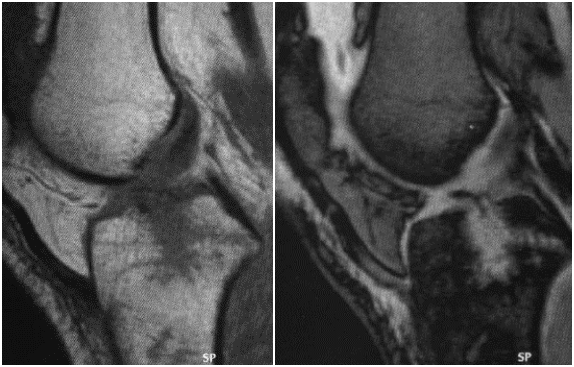

男,30 岁,正常前交叉韧带,T1 及 T2 加权序列矢状面

女,20 岁,正常前交叉韧带,扇形,韧带前为低信号,后为中等信号纤维束

男 40 岁,正常前交叉韧带,扇形,前为低信号,后为中等信号纤维束